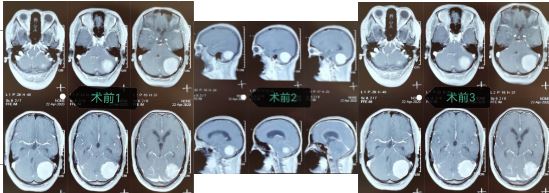

近日,我院神经外科一病区成功完成两例后颅窝病变术,经手术治疗后患者痊愈出院。这是我院神经外科首次独立完成的后颅窝病变术,术后患者恢复良好,无手术并发症,标志着我院神经外科在颅内肿瘤手术技术上又迈上一个新的台阶。

患二:女性,47岁,主因“头痛、头晕2月余”来我院门诊就诊,经颅脑MRI检查提示:左侧小脑幕占位,颅脑MRI增强检查提示:左侧小脑幕脑膜瘤。诊断明确后,收住神经外科一病区。入科后,经术前充分准备,在神经外科一病区医护团队的共同努力下,为患者进行了“左侧小脑幕脑膜瘤切除术”,术中完全切除肿瘤组织,术后患者完全康复,未留任何后遗症,手术取的圆满成功。术后,患者为表达感激之情,特赠送神经外科一病区锦旗一面。